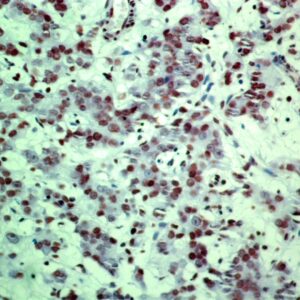

BioGenex has pioneered the development of miRNA research and diagnostics tools with leading-edge products. Currently, we offer over 240 ready-to-use (RTU) Super Sensitive™ Nucleic Acid (SSNA) miRNA ISH probes for accurate and early tumor diagnosis. These probes are sensitive enough to detect low-abundant miRNA(s) that are often required to identify biomarkers. They have a high melting temperature enabling stringent washes to remove non-specific binding. BioGenex miRNA probes are dual-end labeled with an anti-fluorophore to amplify the signal and yield clean and intense staining.